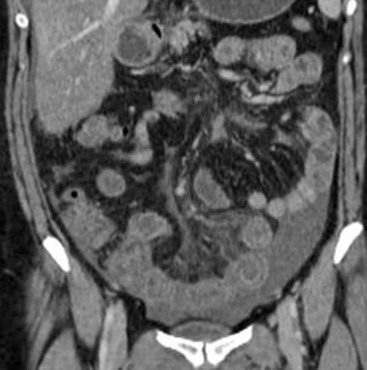

MDCT with coronal and sagittal reformations (Fig. 30-19) is considered the optimal technique for detecting the presence, location and extent of peritoneal carcinomatosis; overall diagnostic accuracy of 94%, specificity of 92% and sensitivities between 75 and 81% have been reported;22 however, sensitivity for identifying small lesions by MDCT is significantly lower. Implantation of tumour deposits along the peritoneal surfaces of the diaphragm, liver and spleen results in smooth, nodular, or plaque-like thickening and contrast enhancement of the parietal peritoneal lining. However, these features are not specific for peritoneal carcinomatosis as they may be seen with other processes that seed the peritoneum, including tuberculosis, peritoneal mesothelioma and peritoneal lymphomatosis. Contrast-enhanced T1-weighted MR images with fat saturation can improve the detection of smaller or equivocal implants or of numerous very small implants that may be manifested as a contiguous ‘line-type’ enhancement along the peritoneal surfaces (Fig. 30-20). Peritoneal tumours often enhance slowly and are best seen on images obtained 5 min after injection of gadolinium. The combination of diffuse-weighted images (DWI) and conventional MRI improves the accuracy of MRI for depicting peritoneal implants;23 therefore, DWI is suggested as an indispensable part of any MRI evaluation in patients suspected for PC.23 DW-MRI and FDG-PET/CT are promising methods for the evaluation of peritoneal carcinomatosis,23,24 but still have a limited role, especially for the identification of disease relapse after treatment. Calcification within peritoneal implants before chemotherapy suggests that the primary site is either serous papillary cystadenocarcinoma of the ovary, or, rarely, gastric carcinoma (Fig. 30-21).

The evolution of cytoreductive surgery (CRS) has revolutionised the treatment of PC and is a challenge for imaging. Cytoreductive surgery aims at complete resection of tumour-bearing peritoneal surfaces and abdominal organs. Optimal CRS requires excision of any visible malignant peritoneal deposit. Complete CRS is often followed by hyperthermic intraperitoneal chemotherapy (HIPEC) to eliminate minimal residual PC. CRS with HIPEC is associated with significantly improved, progression-free and overall survival. Imaging techniques have an important role in the preoperative evaluation of PC and in the selection of candidates for CRS-HIPEC. Analysis of imaging findings should be performed on a site-by-site basis and the presence, type and size of peritoneal seeding should be reported in every region of the peritoneal cavity. Preoperative assessment of the overall disease burden and the extent of involvement in specific peritoneal areas are of decisive significance in the selection of patients that could benefit from CRS and in surgical planning.25 For example, extensive involvement of the hepatoduodenal ligament or of the small-bowel mesentery may preclude a complete CRS, while infiltration of the ligaments suspending the stomach by PC may indicate the need for gastrectomy (Fig. 30-22).